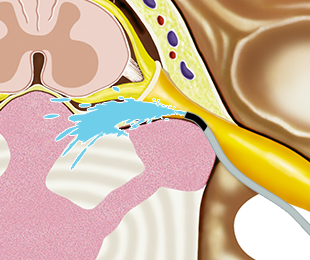

1차 약물을 쏘아 각종 유착을 박리함

04

유착이 박리되고 부어있던 신경이 겉으로 드러남

05

2차로 염증을 가라앉히는 약물을 투여

신경성형술은 유착된 디스크와 신경염증으로 인해 약물이 병변까지 도달하지 못하고 흘러 나오는 문제를 개선하여 실시간 영상을 통해 정확한 병변 부위를 확인하며 약물을 직접 주입함으로써 유착을 없애고 염증을 완화시켜줍니다.